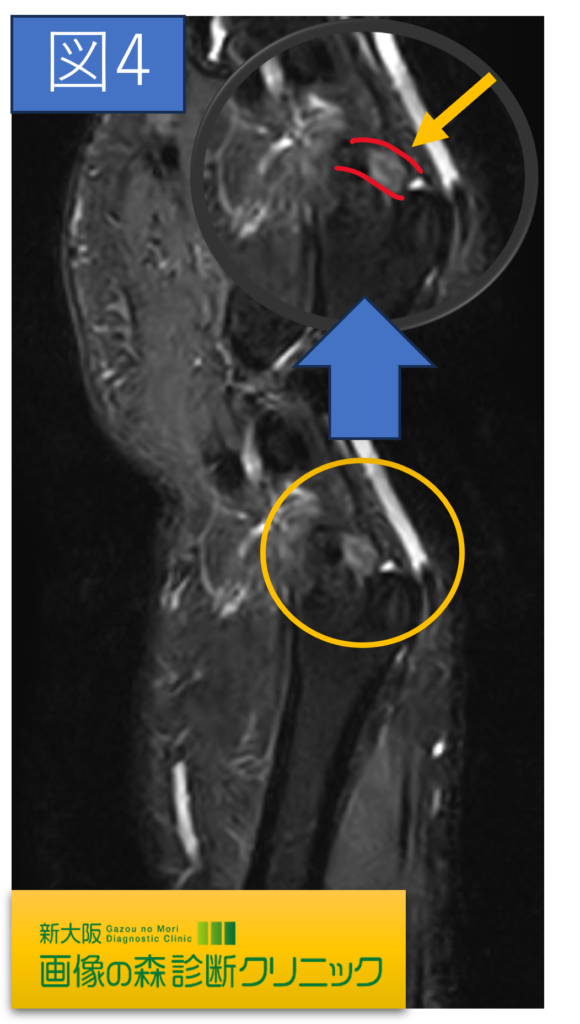

TFCC損傷MRI画像(矢状断像)

症例画像から図2・図4 〇内にTFCCの損傷を示しています。

正常では靱帯や腱は黒く描出されますが、損傷では、白く高信号に描出されます。